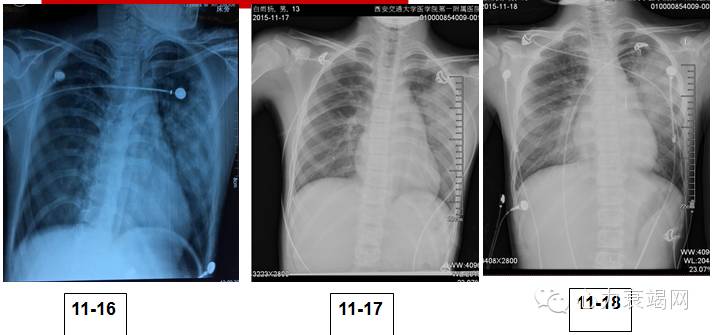

胸片

入院第二天(11-17),患者气短明显,血压进行性下降转入心内CCU病房,治疗处理:

入院第3天,患者气短,意识模糊,皮肤湿冷,出现心源性休克征象。治疗处理:

入院第4天至第14日,患者患者意识好转,呼吸、血压恢复,逐渐停用升压药,治疗处理: